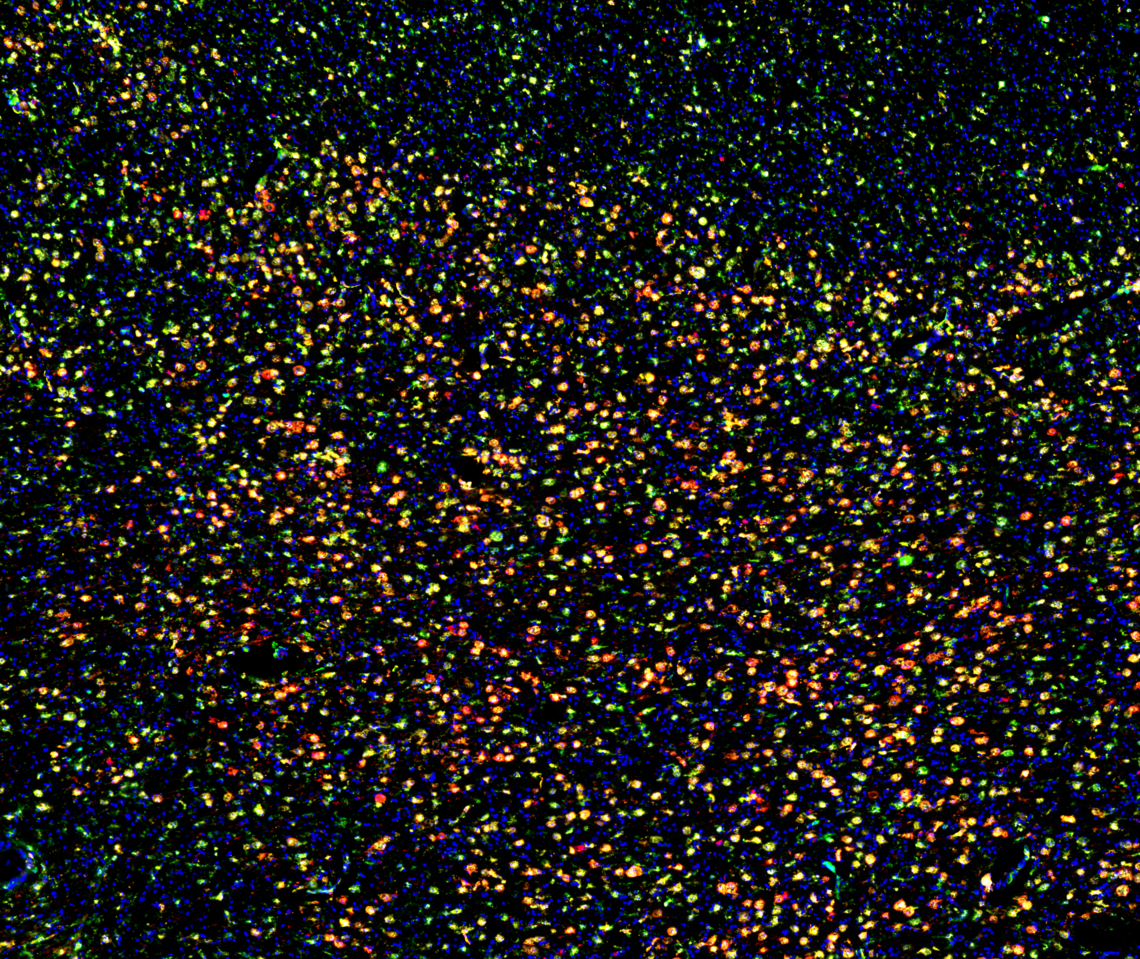

A massive perivascular cuff in EAE mouse cerebellum. Laminin- basement membranes, CD45-Immune cells

Investigating EMMPRIN as a mediator of MS pathology

I am researching the mechanisms of leukocyte trafficking into the brain during multiple sclerosis (MS) pathogenesis. Using the Experimental Autoimmune Encephalomyelitis (EAE) mouse model for MS, I am working on a project pertaining to understanding the metabolic requirements and its underlying mechanisms within myeloid cells in EAE/MS. In this regard, I am investigating the role of Extracellular Matrix Metalloproteinase Inducer (EMMPRIN) in governing enhanced glycolysis in pro-inflammatory myeloid cells. Using genetic tools to conditionally ablate EMMPRIN from CCR2+ monocytes (CCR2Cretm:EMMPRINfl/fl mice), I am currently studying its involvement in mediating EAE/MS pathology. In addition to my interests in monocyte/macrophages, I am also looking into the pathogenic role of pericytes and astrocytes.